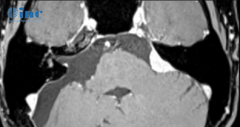

脑膜瘤(小脑)

桥小脑角区 脑膜瘤 ,通常压迫周围许多重要神经血管、小脑甚至脑干,大肿瘤,手术难度大,手术不慎易残留肢体瘫痪、面瘫、听力损伤等。完整切除桥...

桥小脑角脑膜瘤占桥小脑角区肿瘤的6-15%。它们的特点是肿瘤位置深、手术范围窄、靠近脑干、多对(XI)脑神经。目前,手术治疗是大型桥小脑角脑膜瘤的优...

桥小脑角(cerebellopontineanglemeningioma,CPA)脑膜瘤在中枢神经系统肿瘤中并不少见,其临床表现一般与肿瘤的起始部位、侵袭结构及肿瘤大小有关。CPA的颅神经包...

CPA桥小脑角区肿瘤约占成人全部颅内肿瘤的10%。脑膜瘤是二常见的肿瘤官方认可的桥小脑角区肿瘤,前庭神经鞘瘤之后,是生长缓慢的良性病变,通常可以...